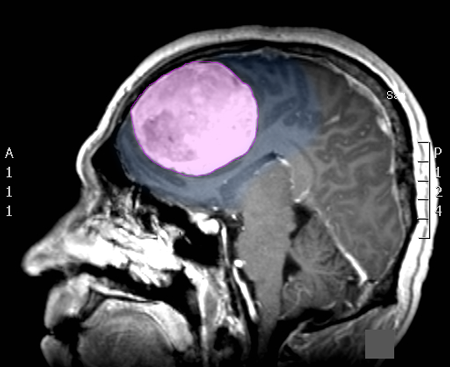

Τα μηνιγγιώματα του εγκεφάλου είναι οι πιο συχνά διαγνωσκόμενοι πρωτοπαθείς όγκοι της κρανιακής κοιλότητας. Εκφύονται από τις μήνιγγες, τα ινώδη περιβλήματα, του εγκεφάλου και είναι, στο μεγαλύτερο ποσοστό τους, καλοήθεις με αργή ανάπτυξη. Ανάλογα με τη θέση και το μέγεθος τους μπορεί να προκαλέσουν διάφορα συμπτώματα όπως επιληπτικές κρίσεις, αδυναμία ή/και υπαισθησία (μούδιασμα) σε ένα ή περισσότερα άκρα, διαταραχές του λόγου ή της όρασης, κ.α. Όχι σπάνια ανακαλύπτονται τυχαία σε απεικονιστικούς ελέγχους μη έχοντας προλάβει να δημιουργήσουν συμπτώματα. Η θεραπεία τους, όταν προκαλούν ή ενδέχεται να προκαλέσουν συμπτώματα είναι χειρουργική, ακτινοχειρουργική ή, σπανιότερα, ακτινοθεραπευτική. |

Επίπτωση και Αιτίες Τα μηνιγγιώματα του εγκεφάλου αποτελούν το 34% των ετησίως διαγνωσκόμενων πρωτοπαθών όγκων του εγκεφάλου και προσβάλλουν συχνότερα τις γυναίκες (η αναλογία προς τους άντρες είναι περίπου 2 έως 3:1). Ανακαλύπτονται πιο συχνά σε ηλικίες ανάμεσα στα 40-70 έτη. Το 90% από αυτά είναι καλοήθη, και μεγαλώνουν αργά, με ρυθμό συνήθως μερικών χιλιοστών ανά έτος, το 8% θεωρούνται άτυπα και έχουν μεγαλύτερο ρυθμό ανάπτυξης, και το 2% παρουσιάζουν κακοήθη χαρακτηριστικά. Για την δημιουργία των μηνιγγιωμάτων έχει αποδειχθεί, σε διαφόρους βαθμούς, ότι ενέχονται: παλαιότερη έκθεση σε ιονισμένη ακτινοβολία (όπως π.χ. ακτινοθεραπεία εγκεφάλου), ορμονολογικοί παράγοντες (κάποια μηνιγγιώματα φέρουν υποδοχείς οιστρογόνων, προγεστερόνης και ανδρογόνων) και γενετικοί παράγοντες (αυξημένη επίπτωση σε ασθενείς με π.χ. νευροϊνωμάτωση). Στα περισσότερα μηνιγγιώματα η αιτία της δημιουργίας τους δεν μπορεί να απομονωθεί ή να αποδειχθεί, όπως συμβαίνει με τους περισσότερους καλοήθεις όγκους. |

Συμπτώματα Τα συμπτώματα των μηνιγγιωμάτων ορίζονται από τον συνδυασμό της θέσης και του μεγέθους τους. Μικρά μηνιγγιώματα σε επαφή και με πίεση επί ευγενών περιοχών του εγκεφάλου, όπως αυτές που ελέγχουν την κίνηση, τον λόγο ή την όραση μπορεί να προκαλέσουν περισσότερα συμπτώματα από πολύ μεγαλύτερα σε μέγεθος μηνιγγιώματα που πιέζουν λιγότερο σημαντικές περιοχές. Τα συχνότερα συμπτώματα είναι οι επιληπτικές κρίσεις, η αδυναμία ή/και η υπαισθησία (μούδιασμα) σε ένα ή περισσότερα άκρα και οι διαταραχές του λόγου και της όρασης. Όπως προαναφέρθηκε τα μηνιγγιώματα μπορεί να ανακαλυφθούν τυχαία σε απεικονιστικό έλεγχο του εγκεφάλου για διαφορετικούς λόγους, χωρίς να έχουν προκαλέσει (ακόμη) κανένα σύμπτωμα |

Διάγνωση Απαραίτητα είναι: Η λεπτομερής λήψη ιστορικού και η κλινική εξέταση, Η μαγνητική τομογραφία του εγκεφάλου με σκιαγραφικό, Σε ορισμένες περιπτώσεις: Η μαγνητική αγγειογραφία ή/και φλεβογραφία του εγκεφάλου, Η μαγνητική τομογραφία του εγκεφάλου με σκιαγραφικό για νευροπλοήγηση, Ηλεκτροεγκεφαλογράφημα και άλλες εξειδικευμένες εξετάσεις όπως μέτρηση οπτικής οξύτητας και οπτικών πεδίων προτείνονται κατά περίπτωση. |